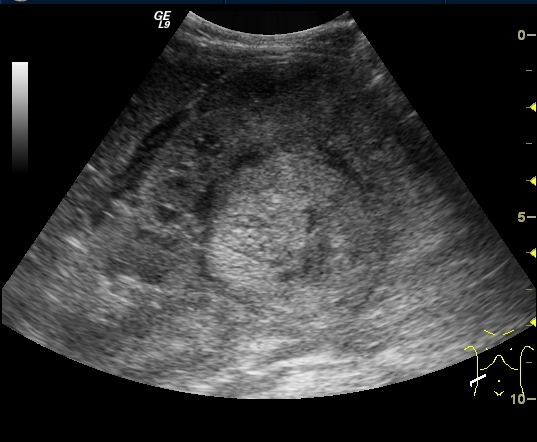

Wilms tumor. It is the most common kidney tumor in childhood that appears between 2-5 years of age. It is usually only noted when the tumor is palpable as an abdominal mass. Hematuria, hypertension, vomiting and abdominal pain are also part of the clinical picture. US examination is a basic method in both the diagnostics and the follow-up of the tumor. The tumor is normally seen as a homogenous or an inhomogeneous mass, dislocating the pyelon and the surrounding retroperitoneal blood vessels. It is important to rule out any lesion in the other kidney. MRI examination: gives a picture of the entire abdomen, kidneys included. Nodal metastases, tumor thrombus are well depictable. CT-examination: is to be chosen if MRI is not available. The tumor shows an inhomogeneous contrast enhancement and pulmonary metastases (invisible to x-ray examination) are also depictable.

27. A solid, echogenic mass arising from the right kidney. Wilms tumor. Abdominal US.